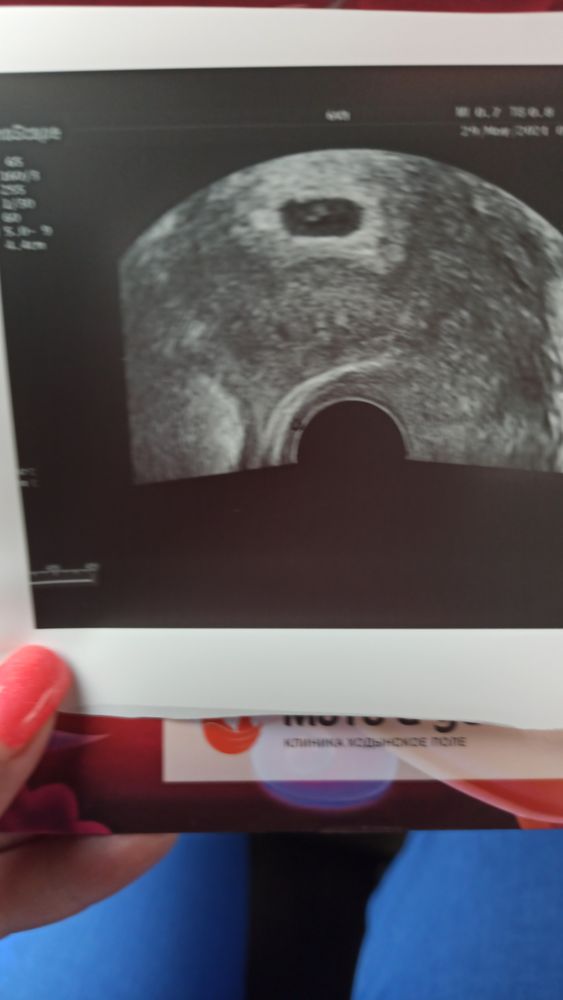

24 дпп-Узи💞

Я БЕРЕМЕННА !Как же я счастлива ,боженька услышал наши молитвы 🙏мы беременны 🤰. Доктор хотела нас наблюдаться в жк отправить , но мы решили что еще встретимся через две недельки с ней . назначала сдать доп анализы гемостаз +д диммер+ волчаночный антикоагулянт.